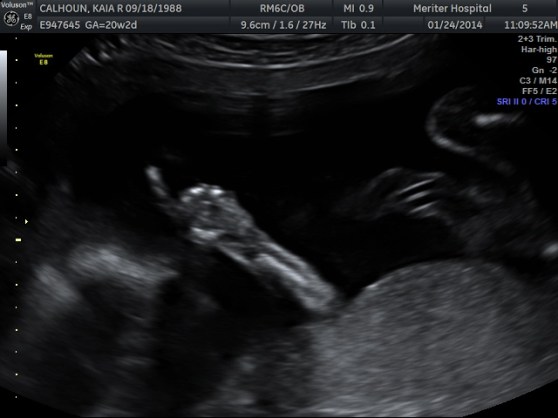

To keep up with our surprise baby announcement tactic I wrote Grandma and Grandpa a Christmas card with a Christmas poem announcing the summer arrival of their first great-grandchild. And now, I’ll let the video do the rest of the talking 🙂 I have posted the words to the Christmas poem grandma is reading below the video.